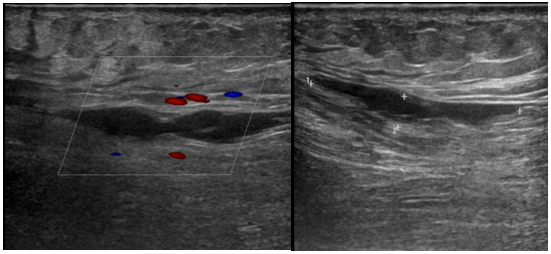

Hình 4: Huyết khối tĩnh mạch đùi – khoeo trái trên siêu âm

Bệnh nhân nữ, 65 tuổi, nhập viện vì phù cẳng chân trái. Bệnh nhân không ghi nhận tiền căn bệnh lý tim mạch trước đây. Cách nhập viện khoảng 3 tuần, bệnh nhân thấy đau cẳng chân trái tăng dần. Cách nhập viện khoảng 1 tuần, bệnh nhân thấy chân trái đau nhiều, hạn chế đi lại, kèm sưng phù chân trái nên nhập viện. Khám ghi nhận, sinh hiệu trong giới hạn bình thường, không sốt: mạch = 80 lần/phút, HA = 130/80 mmHG, nhiệt độ = 36,8oC, nhịp thở = 20 lần/phút, SpO2 = 98%/khí trời. Khám ghi nhận sưng phù chân trái, đường kính chân trái lớn hơn chân phải. Điện tâm đồ trong giới hạn bình thường. Siêu âm tĩnh mạch chi dưới ghi nhận: huyết khối không hoàn toàn giai đoạn cấp – bán cấp các tĩnh mạch sâu và tĩnh mạch nông đùi trái (tĩnh mạch đùi, tĩnh mạch khoeo, tĩnh mạch hiển bé) và huyết khối không hoàn toàn ở đoạn đầu tĩnh mạch chày sau và tĩnh mạch chày trước bên trái.

Bệnh nhân ổn định sau điều trị 3 ngày, tình trạng chân trái giảm sưng phù, giảm đau và xuất viện uống kháng đông Rivaroxaban 15mg x 2 lần/ ngày. Sau xuất viện 01 tuần, bệnh nhân tái khám, giảm đau chân trái. Siêu âm tĩnh mạc lúc tái khám ghi nhận: tĩnh mạch đùi, khoeo và tĩnh mạch cơ bụng chân trái ấn xẹp hoàn toàn, không huyết khối. Huyết khối bám thành tĩnh mạch đùi chung trái và huyết khối không hoàn toàn và bám thành tĩnh mạch hiển bé.

Hình 8: Siêu âm tại thời điểm tái khám